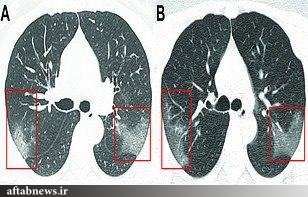

سرویس سلامت- تصاویر گرفته شده با اشعه ایکس نشان میدهند ویروس مرگبار کرونا تا چه اندازه بر روی اندامهای حیاتی فرد مبتلای ۳۳ ساله تاثیر گذاشتهاند.

به گزارش آفتابنیوز؛ این تصاویر متعلق به زنی ۳۳ ساله و بستری شده در بیمارستان لانژو در چین است که پیش از انتقال به بیمارستان در ووهان به ویروس کرونا مبتلا شده بود.

درجه دمای بدن او ۱۰۲ فارنهایت یا ۳۹ درجه سانتیگراد ثبت شده است. علائم آشکار شده بر روی ریه فرد به صورت تکههای سفید رنگ قابل مشاهده هستند.